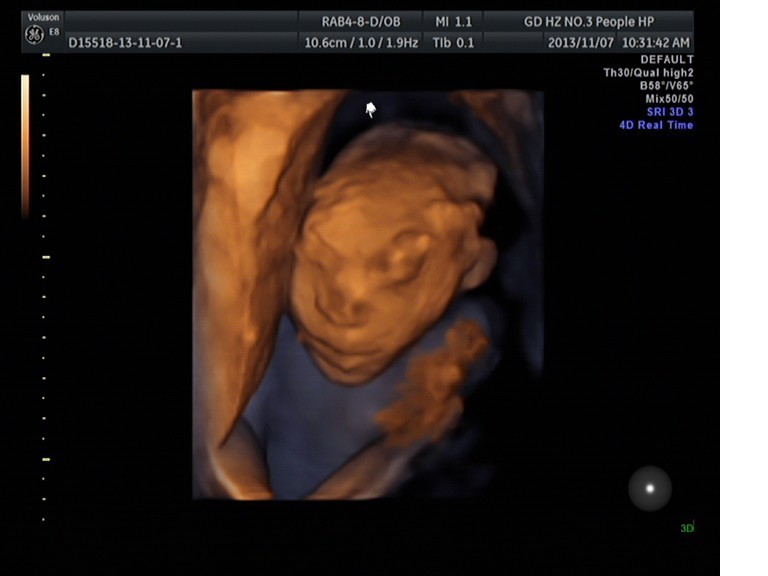

我院超聲科篩查出多例腦膜腦膨出畸形胎

近期我院超聲科在胎兒早中孕篩查時(shí)發(fā)現(xiàn)多例腦膜腦膨出的畸形胎兒。其中一例是目前我院發(fā)現(xiàn)最早的腦膜腦膨出畸形胎,孕約12周多。當(dāng)時(shí)那個(gè)孕婦是過來做胎兒早期NT篩查的,超聲科曾曦醫(yī)生檢查時(shí)發(fā)現(xiàn)胎兒顱骨光環(huán)回聲中斷,可見混合性腫塊突出,并且NT值偏高,可疑腦膜腦膨出。于是曾曦醫(yī)生立即邀請馬曉芹主任過來會(huì)診,結(jié)果證實(shí)了該胎兒的確有腦膜腦膨出畸形,建議終于妊娠。

腦膨出超聲診斷要點(diǎn)是胎兒顱骨高回聲環(huán)的延續(xù)性中斷,局部向外突出囊性物,使頭部變形。根據(jù)囊內(nèi)容物回聲特征可判斷膨出物來源。若囊內(nèi)為液性暗區(qū)則為腦膜膨出,內(nèi)為實(shí)性的腦組織結(jié)構(gòu)則為腦膜腦膨出。在鑒別診斷上,腦膜膨出容易與囊狀淋巴管瘤相混淆,但囊狀淋巴管瘤時(shí),骨質(zhì)無缺損,顱骨是完整的。超聲醫(yī)生應(yīng)進(jìn)行多方位、多切面的仔細(xì)掃查,方能為臨床終止妊娠提供可靠的依據(jù)。

胎兒腦膜腦膨出是臨床上胎兒發(fā)育中先天性畸形的一種,對其作出早期診斷非常重要。我院引進(jìn)了目前全球最領(lǐng)先的以胎兒四維彩超為主的高分辨率全身彩色多普勒超聲診斷儀Voluson E8,先進(jìn)的設(shè)備加上優(yōu)秀的人才,使得我院超聲科的診斷水平越來越高,使得我們對胎兒畸形篩查的把關(guān)口已經(jīng)從中孕期(孕約2025周)提前到早孕NT期(孕1114周)。這樣不單單可以對部分先天性胎兒畸形可以作出早期診斷、及時(shí)終止妊娠,還可以大大減少對孕婦身體的傷害,更多的是減少這些家庭的經(jīng)濟(jì)壓力與精神負(fù)擔(dān)。